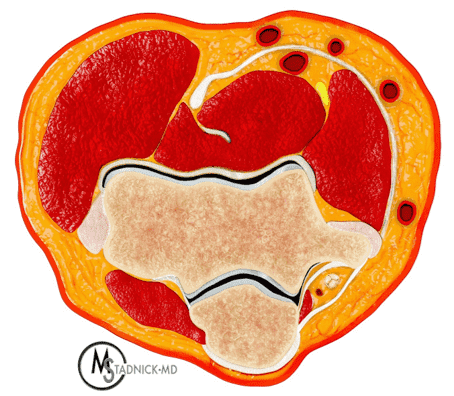

The cubital tunnel is a fibro-osseous space along the dorsoulnar aspect of the elbow joint, roughly triangular in cross-section (Figure 3). The medial humeral epicondyle and olecranon process of the proximal ulna form the anterior and lateral walls of the tunnel, respectively. A myofascial retinaculum joining these two bones (Osborne’s ligament) comprises the roof of the tunnel, and more distally the cubital tunnel retinaculum blends with a tendonous band that connects the two heads of the flexor carpi ulnaris muscle.4 Anatomic variations of the cubital tunnel retinaculum are common, and can contribute to the development of ulnar nerve pathology.5 The distal-most fibers of the medial head of the triceps muscle may extend into the proximal cranial portion of the cubital tunnel along the medial aspect of the olecranon. The posterior band of the ulnar collateral ligament (UCL) and the elbow joint capsule lie along the floor of the tunnel.6 The ulnar nerve and the posterior ulnar recurrent artery are located within the tunnel, surrounded by loose connective tissue and fat. The nerve can have one to several macroscopic fascicles, which may be visible on high-resolution ultrasound or fluid-weighted MRI studies (Figure 4).7,8

Figure 3: Normal cross-sectional anatomy of the cubital tunnel. (3A) Drawing showing a cross section of the elbow (3A) and an enlargement of the cubital tunnel (3B). The cubital tunnel retinaculum forms the roof of the tunnel. The posterior band of the ulnar collateral ligament and the posteromedial elbow joint capsule lie along the tunnel floor, and the distal muscle belly of the medial head of the triceps is present adjacent to the olecranon. The ulnar nerve and a branch of the ulnar artery are the main structures within the tunnel. Axial T1-weighted image (3C) demonstrates the corresponding anatomy: O = olecranon process of the proximal ulna, ME = medial humeral epicondyle, t = medial head triceps muscle, blue arrow = elbow joint capsule, red arrow = posterior band of the ulnar collateral ligament, arrowheads = cubital tunnel retinaculum, asterisk = ulnar nerve. The posterior ulnar recurrent artery is the round structure along the posterolateral aspect of the ulnar nerve.